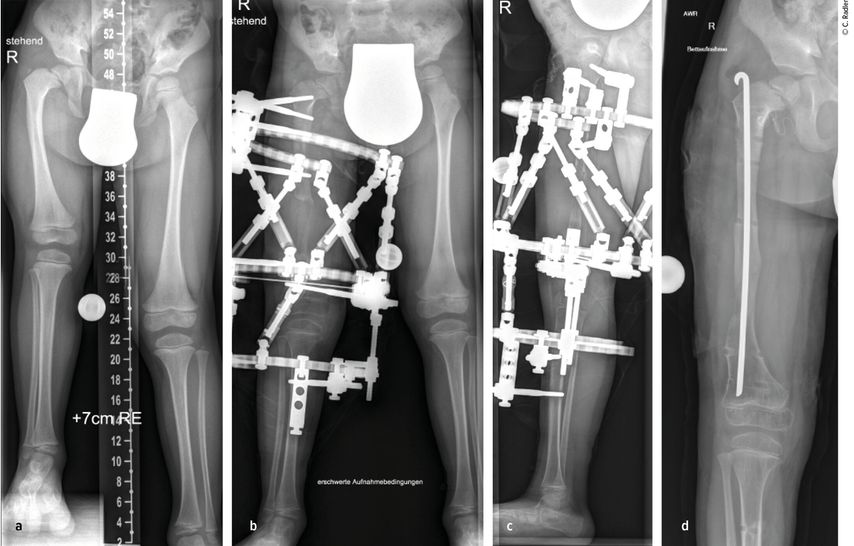

Milde Formen – Typ 1A – zeigen oft nur einen leichten Schenkelhalsvarus und eine verminderte femorale Antetorsion beziehungsweise Retroversion zusätzlich zur Verkürzung. Oft zeigt sich bei diesem Typ auch eine milde subtrochantäre Varusstellung und Sklerose. Mit zunehmendem Schweregrad addiert sich eine azetabuläre Dysplasie, wobei besonders die obere und hintere Überdachung der Hüfte vermindert ist. Beim Typ 1A ist in seltenen Fällen keine vorbereitende Operation erforderlich, insbesondere wenn die Überdachung der Hüfte sehr gut ist und ein CE-Winkel von über 20 Grad vorliegt. Es kann dann direkt mit einer Verlängerung des Femurs begonnen werden. Je nach verwendeter OP-Technik können eine eventuell vorhandene Retroversion und Varusstellung im Rahmen der Verlängerungsoperation akut über eine zusätzliche proximale Osteotomie und Montage an den oberen Teil des Fixateurs adressiert werden. (Abb.1).

Abb. 1: Operative Versorgung eines CFD rechts mit Varusstellung an der Hüfte und subtrochantärer Sklerosierung